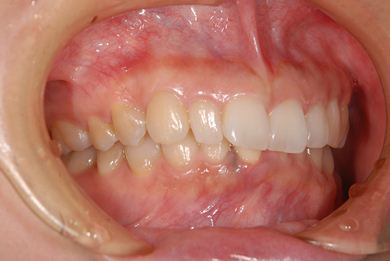

治療後

総治療費 434,805円

治療期間 8ヶ月